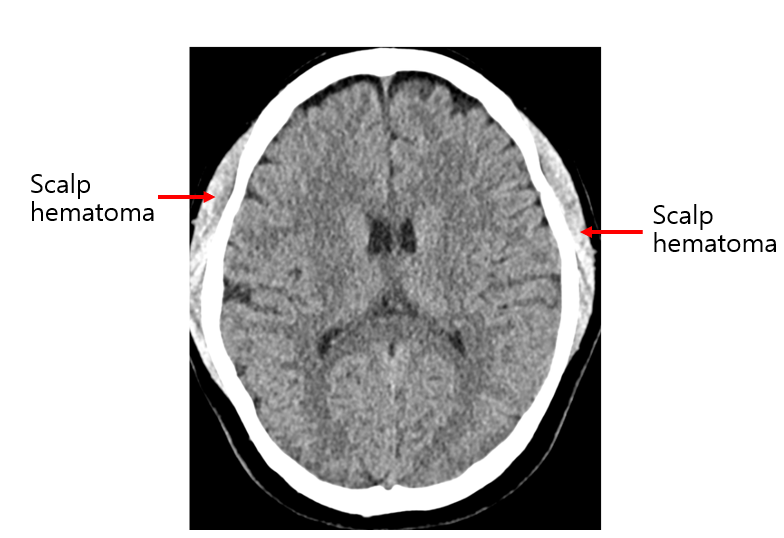

Img | Brain CT: Bilateral scalp hematoma |

외상 후 10분간 기억상실이 있지만 신경계 진찰 모두 정상이며 Brain CT에서 bilateral scalp hematoma 외 다른 이상이 없으므로 뇌진탕으로 진단한다.

• Brain CT에서 bilateral scalp hematoma 외 brain parenchyma 및 epidural, subdural, subarachnoid space에 출혈이 없는 정상소견이므로 경막외출혈, 경막밑출혈, 거미막밑출혈은 모두 배제할 수 있다.